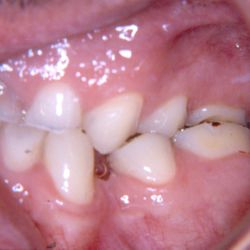

Ο κάτω γομφίος σε αυτή την νεαρή ασθενή έχει απονευρωθεί.

Για να εξασφαλίσουμε την καλή πρόγνωση του δοντιού και ταυτόχρονα την προστασία του από πιθανό κάταγμα, αποφασίστηκε η τοποθέτηση ενός επενθέτου εργαστηριακής σύνθετης ρητίνης.

Η διαδικασία ολοκληρώθηκε σε 2 ραντεβού, ενώ ο τροχισμός του δοντιού διατηρήθηκε στο ελάχιστο δυνατό.

Η εναλλακτική λύση θα ήταν να τροχιστεί εντελώς το δόντι και να τοποθετηθεί μια στεφάνη, οδηγώντας όμως έτσι σε αφαίρεση μεγάλης ποσότητας οδοντικής ουσίας.